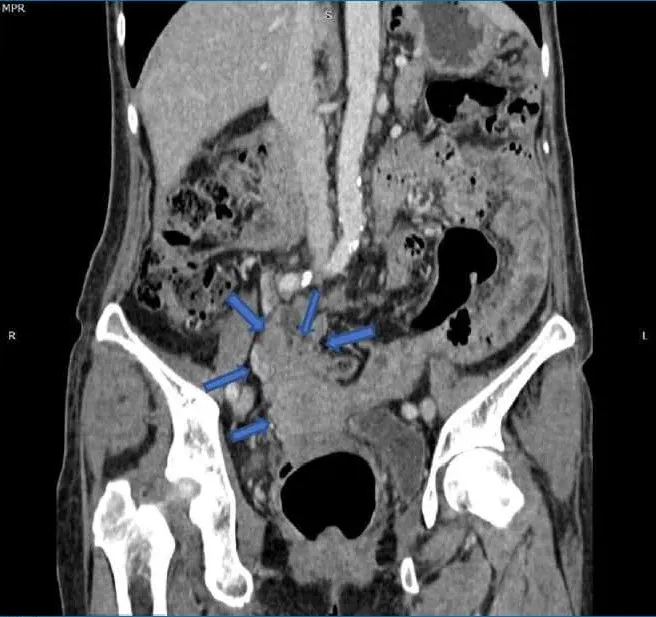

在关节炎出现六个月后,她因腹痛主诉到一家私人医院就诊,接受含网膜活检的小型开腹手术。网膜病理学检查发现II级卵巢浆液性囊腺癌的转移灶沉积。她被诊断为IIIc期卵巢癌,开始新辅助化疗,方案为卡铂(AUC=5,d1)+紫杉醇(80 mg/m2,d1,d8,d15),每21天一周期,共6个周期。SSZ停药。经过三个周期的化疗后,患者出现了新的呼吸道症状。胸部/腹部重复CT显示左侧肺尖后部肿块,双侧肺多发结节,子宫底区域有边界不清的低密度肿块(图3、4)。随后进行了硬质支气管镜检查,发现左上肺叶有一个带蒂肿瘤,几乎完全闭塞了远端左主支气管。肿瘤活检显示为具有肉瘤样特征的恶性肿瘤。

图3. 冠状位计算机断层扫描图像显示:子宫肿块浸润邻近的肠道和大网膜(蓝色箭头)